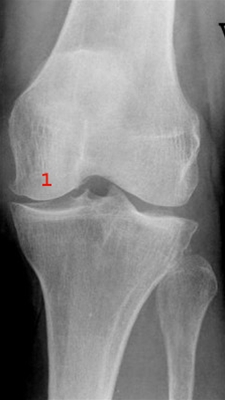

Let reduceret bruskhøjde medialt i knæleddet med mindre knogleudbygning på mediale femurkondyl og tilspidsning af eminentia (1).